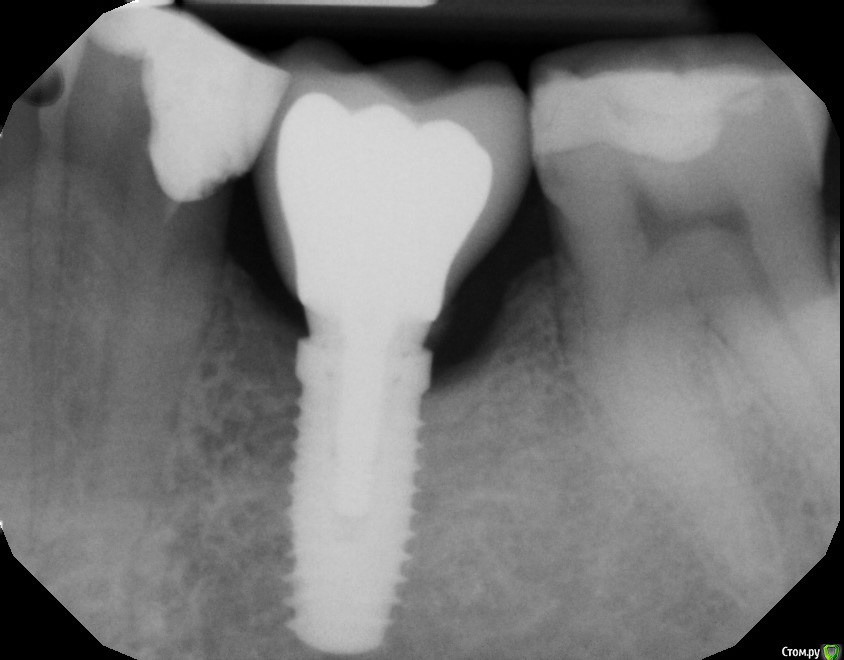

katyarss63 Опубликовано 3 июля, 2017 Поделиться Опубликовано 3 июля, 2017 Ydalyat', ne ydalat'? Pomogite sovetom. Sorri, translit ne rabotaet...Snimki do I posle. Zub bolit vremya ot vremeni. Spasibo za sovety!!! Ссылка на комментарий